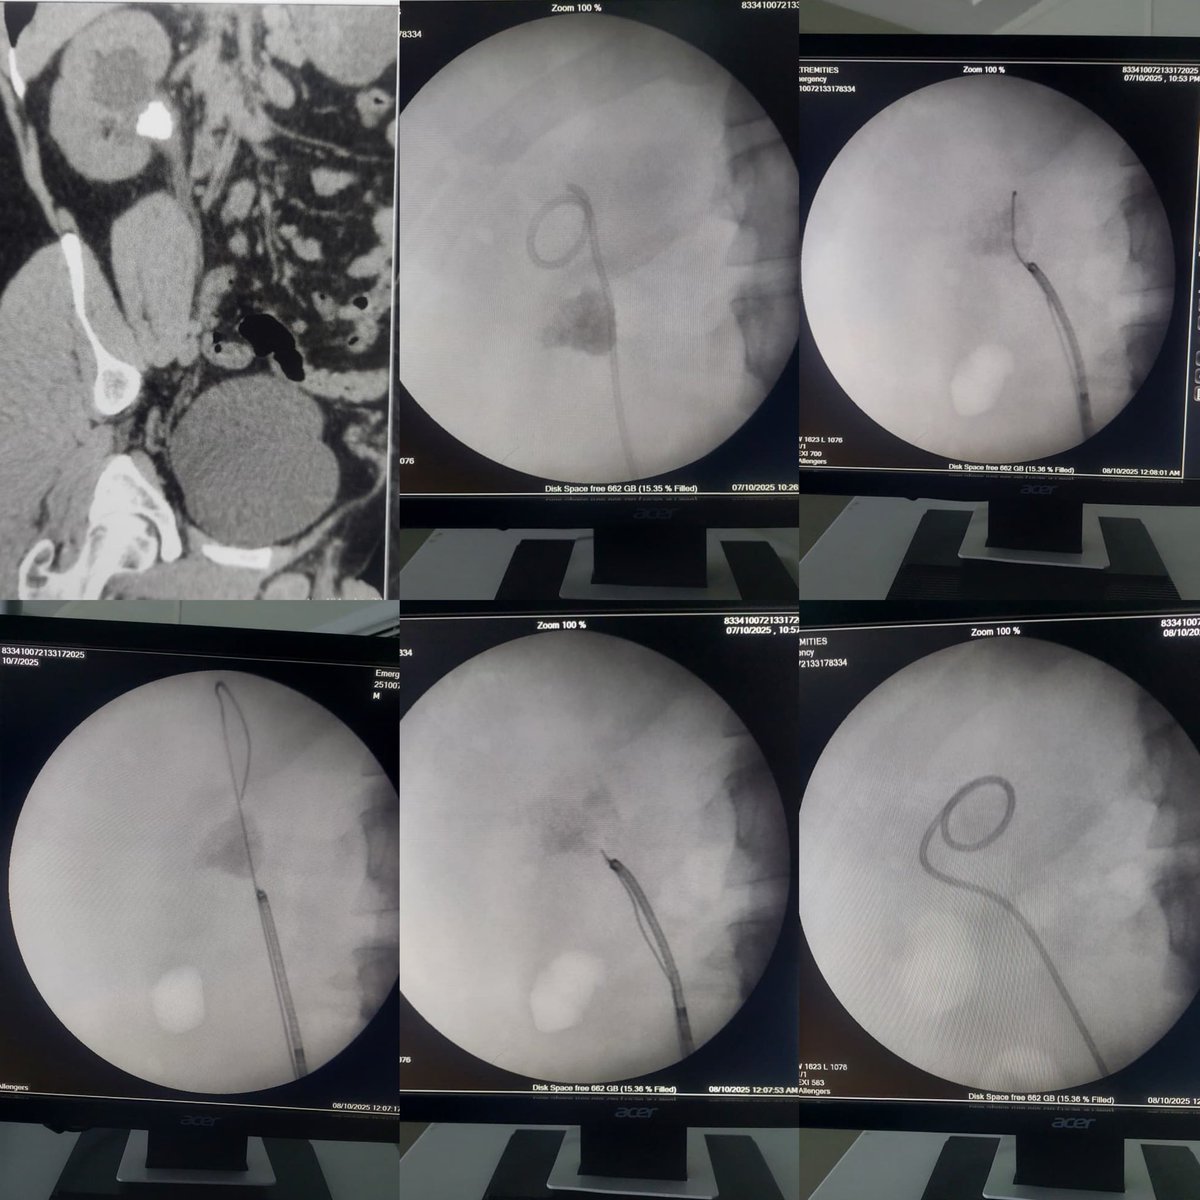

FANS for multiple renal stones. Clearance on table in 40 minutes.

1

3

19

When subcostal lower pole access can not clear all stones, supracostal access saves the case. Happy to be done by my fellow.

2

32